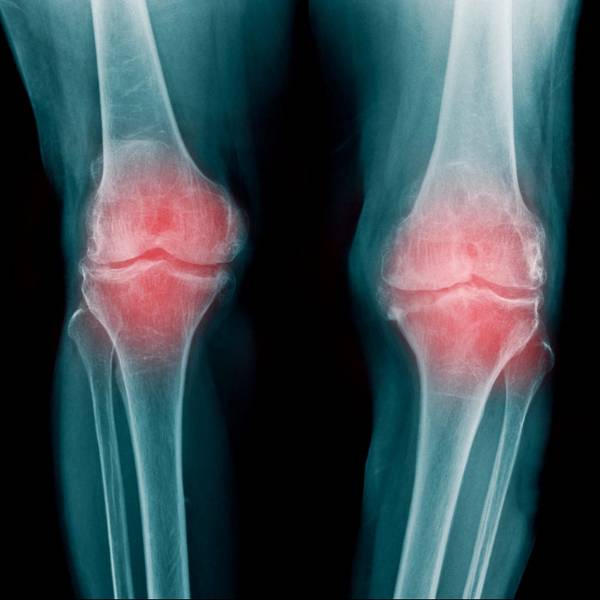

Se trata de una enfermedad crónica y degenerativa que afecta a las articulaciones y conduce a la aparición de dolores y de dificultades que pueden incapacitar seriamente a las personas que la sufren, han recordado los investigadores.

Es además la causa más habitual de dolor y de discapacidad en los adultos y la primera causa de cirugías de reemplazo articular.

En este trabajo, los investigadores provocaron artrosis en la rodilla de ratas jóvenes y luego inyectaron los dos medicamentos experimentales en la articulación de estos animales, y seis semanas después del tratamiento, las ratas que habían recibido esas partículas mostraron una recuperación de su cartílago.

Los investigadores observaron que el cartílago de la rodilla era más grueso, morían menos células y había células que proliferaban activamente, y la enfermedad revirtió hasta una forma "leve" de artrosis (grado I) y no se observaron efectos secundarios negativos.

Por el contrario, las ratas que no habían recibido tratamiento presentaron una artrosis más severa en las rodillas y la enfermedad progresó del grado II al grado IV, el grado máximo de severidad de la enfermedad.